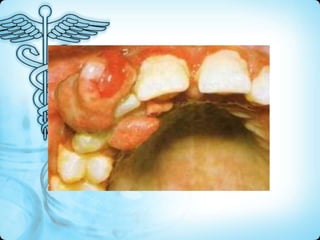

• Brown tumors (resemble CGCG histologically)